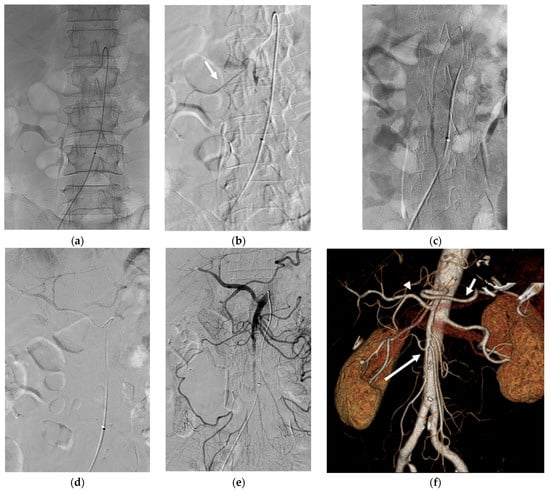

After several attempts, we decided to change our plan of performing embolothrombectomy to thrombolysis using a 5 Fr RH catheter and microcatheter (Progreat Lambda, Terumo, Somerset, NJ, USA) with rtPA. We diluted 5 mg of rtPA in 25 mL of saline and 25 mL of contrast solution to prepare an rtPA solution. Subsequently, the SMA was selectively catheterized using a 5 Fr RH catheter. rtPA (2 mg; 20 mL of rtPA solution) was carefully injected (1 mg per 10 min) through the RH catheter. After thrombolysis, angiography revealed partial recanalization of the proximal SMA and its jejunal and ileal branches (Figure 2). Segmental SMA occlusion with sluggish jejunal flow remained, and no visible colic flow was observed.

Figure 2. After thrombolysis using 2 mg of rtPA via RH catheter, angiography revealed partial recanalization of jejunal and ileal branches of the SMA (arrows).